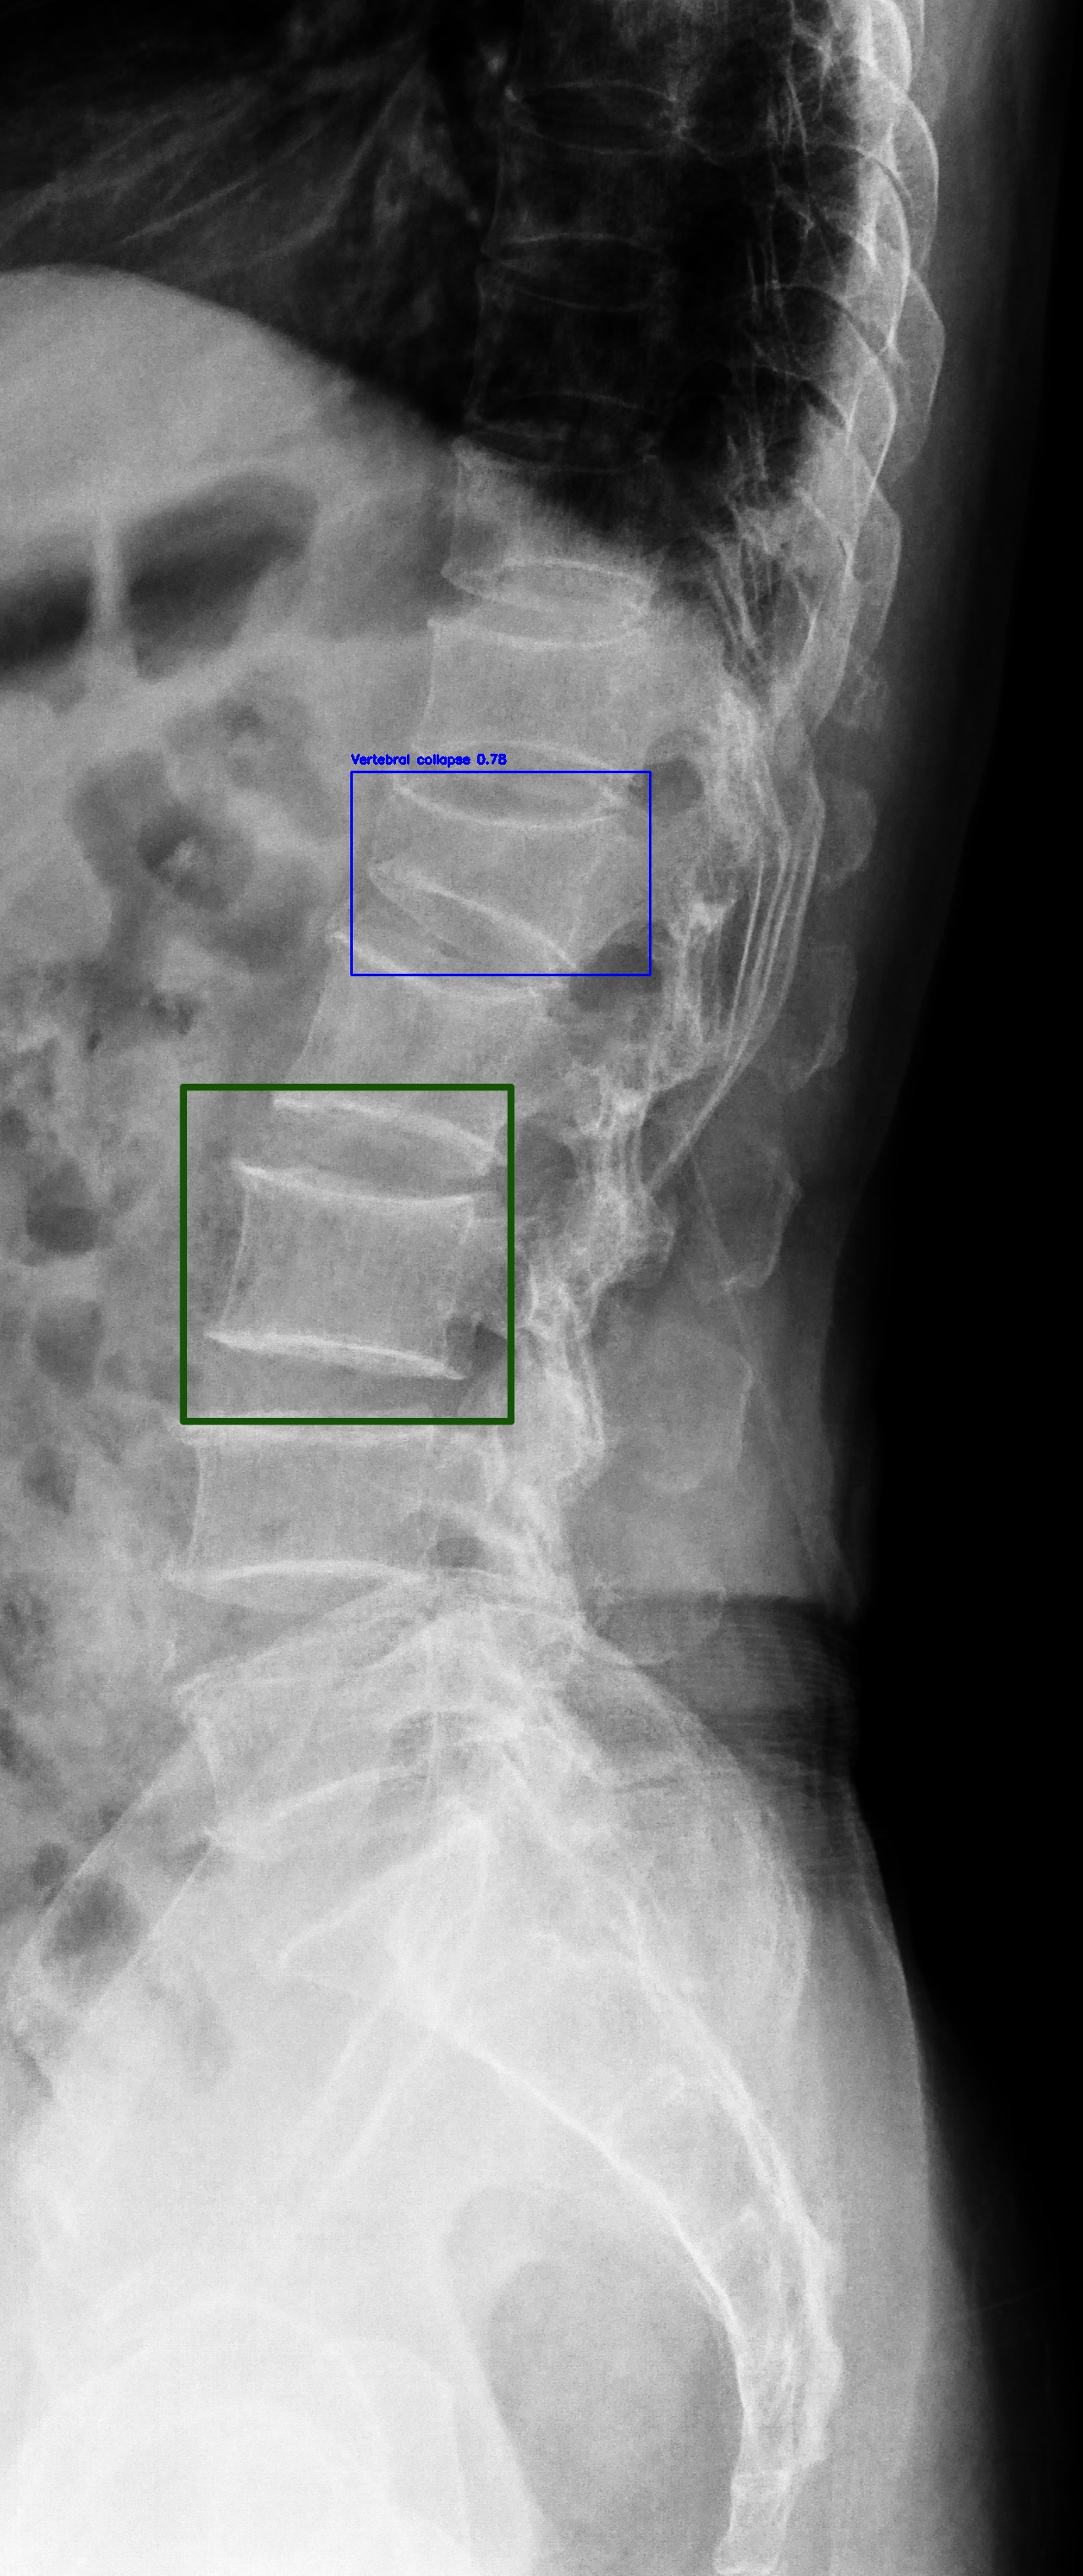

Vertebral Collapse

(a) Vertebral Collapse

Automated Lesion Detection and Localization: Visual demonstration of the cascaded DERNet-YOLO11 framework on VinDr-SpineXR benchmark images. The figure presents eight representative cases including seven pathological conditions with precise bounding-box localization: (a) Vertebral Collapse, (b) Osteophytes, (c) Spondylolisthesis, (d) Surgical Implants, (e) Disc Space Narrowing, (f) Foraminal Stenosis, (g) Other Lesions, alongside (h) a Normal spine radiograph for comparison. Each pathological case demonstrates the model's capability to accurately detect and spatially localize subtle lesions despite significant class imbalance (46.9:1 ratio), small object scales (often <1% of image area), and anatomical structure overlap. The localization boxes validate the clinical applicability of the integrated triage–localization pipeline.